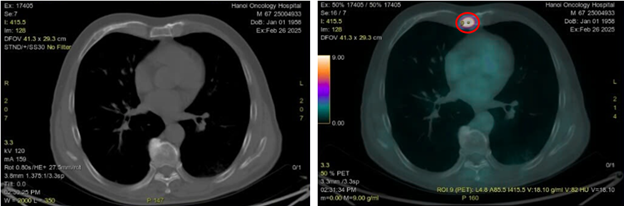

Hình 4: Hình ảnh tổn thương u phổi thùy dưới phổi trái kích thước 10x15mm trên CT (vòng tròn màu vàng) và PET/CT (vòng tròn màu đỏ) tăng chuyển hóa FDG (SUVmax: 9,8)